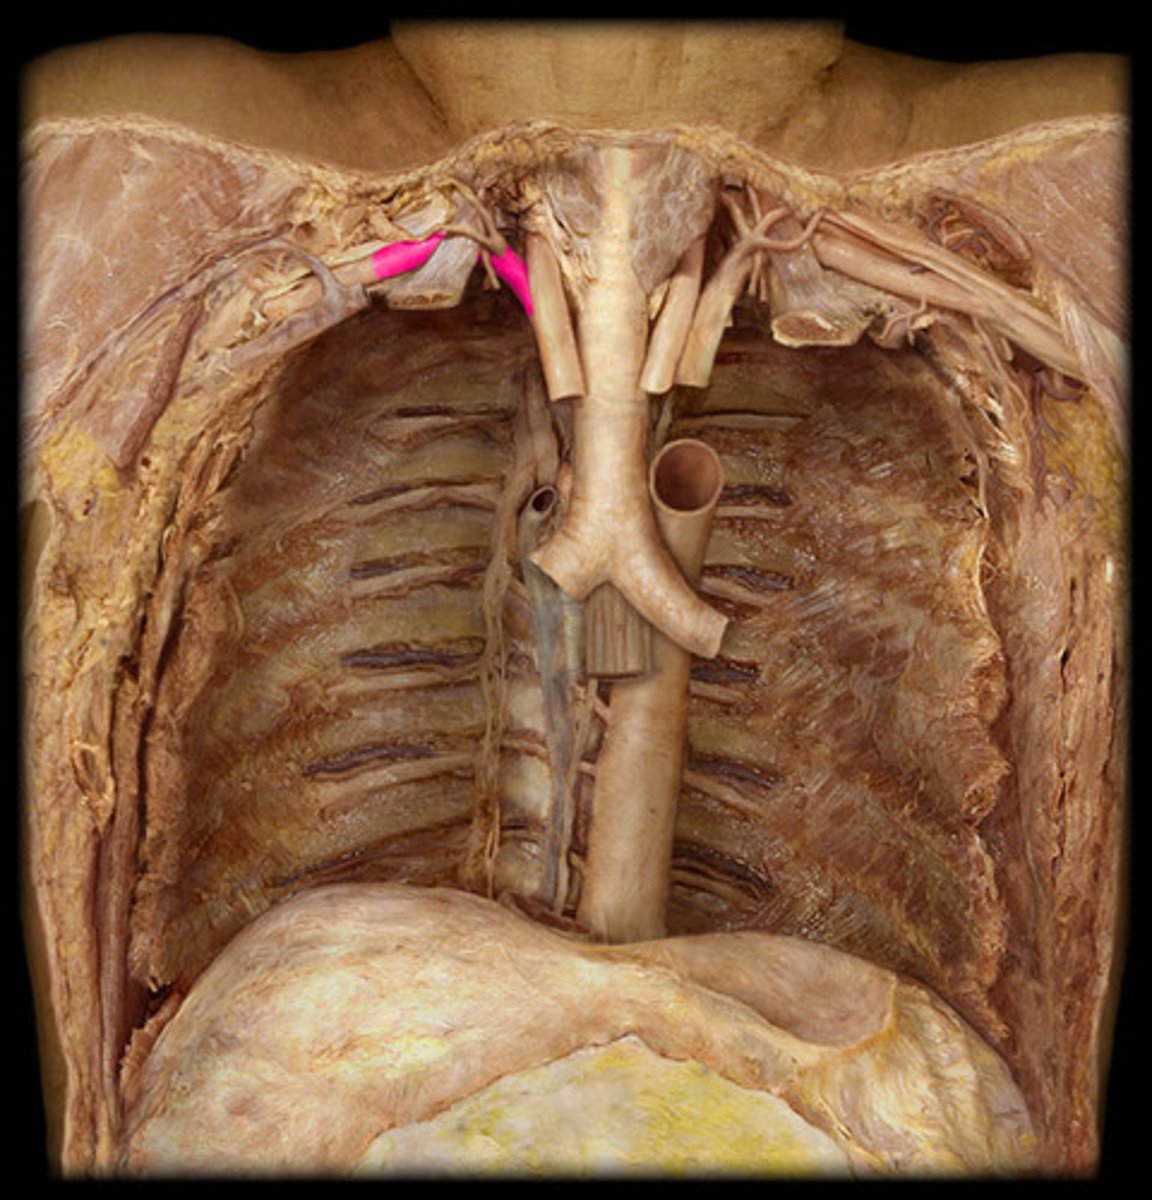

descending aorta

deep to the inferior vena cava; the largest artery of the body; carries blood away from the heart down the midline of the body

thoracic aorta

travels downward through the thorax

left posterior intercostal arteries

enters the 3rd through 11th intercostal spaces, supplies the chest wall

abdominal aorta

continuation of the thoracic aorta that runs through the abdominal cavity